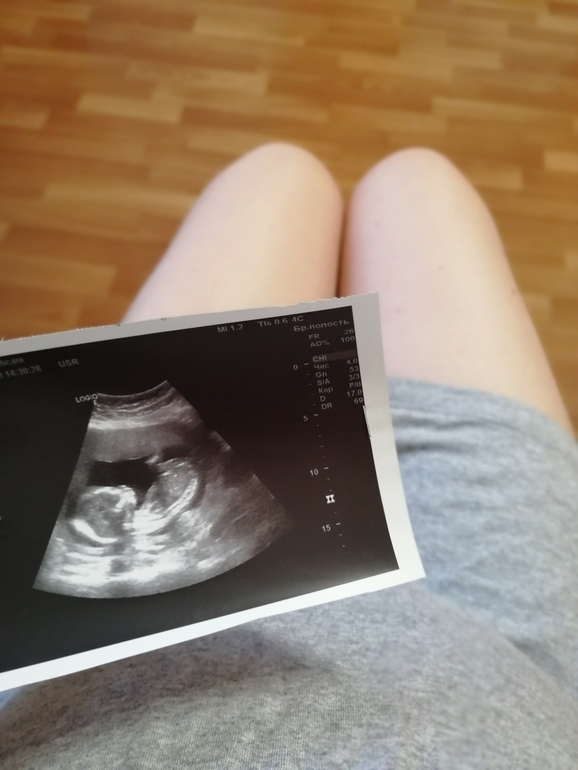

Прошли мы второй скрининг - все отлично! Все параметры в норме. У нас ещё один мальчик 🧒 Сын в восторге - говорит я же братика просил)))

😍малыш фотогеничен😉